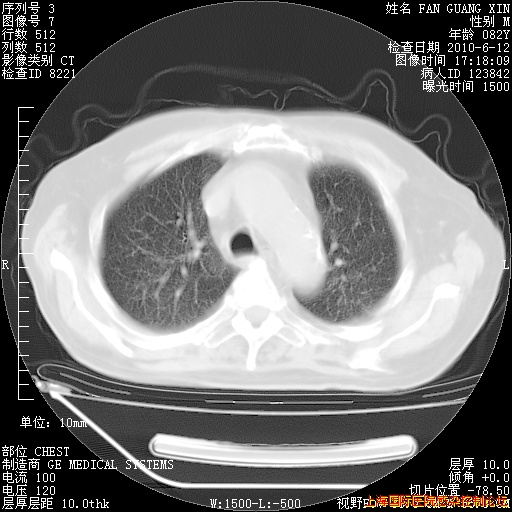

补发6月12日肺部CT肺窗

6月12日肺窗

整整相隔30天的肺部CT好像有所好转啊。甲强龙减量第3天,需要观察体温。

海管,自昨日你和我通完话后,不知您岳父消化道症状有无缓解?体温怎样?阅读7.12日胸部ct,个人认为目前激素治疗是有效的,甲强龙减量是适宜的。因在抗痨治疗,需密切观察肝功、肾功能和血常规。不过,老年、长期住院和大量使用激素,很担心菌群失调发生